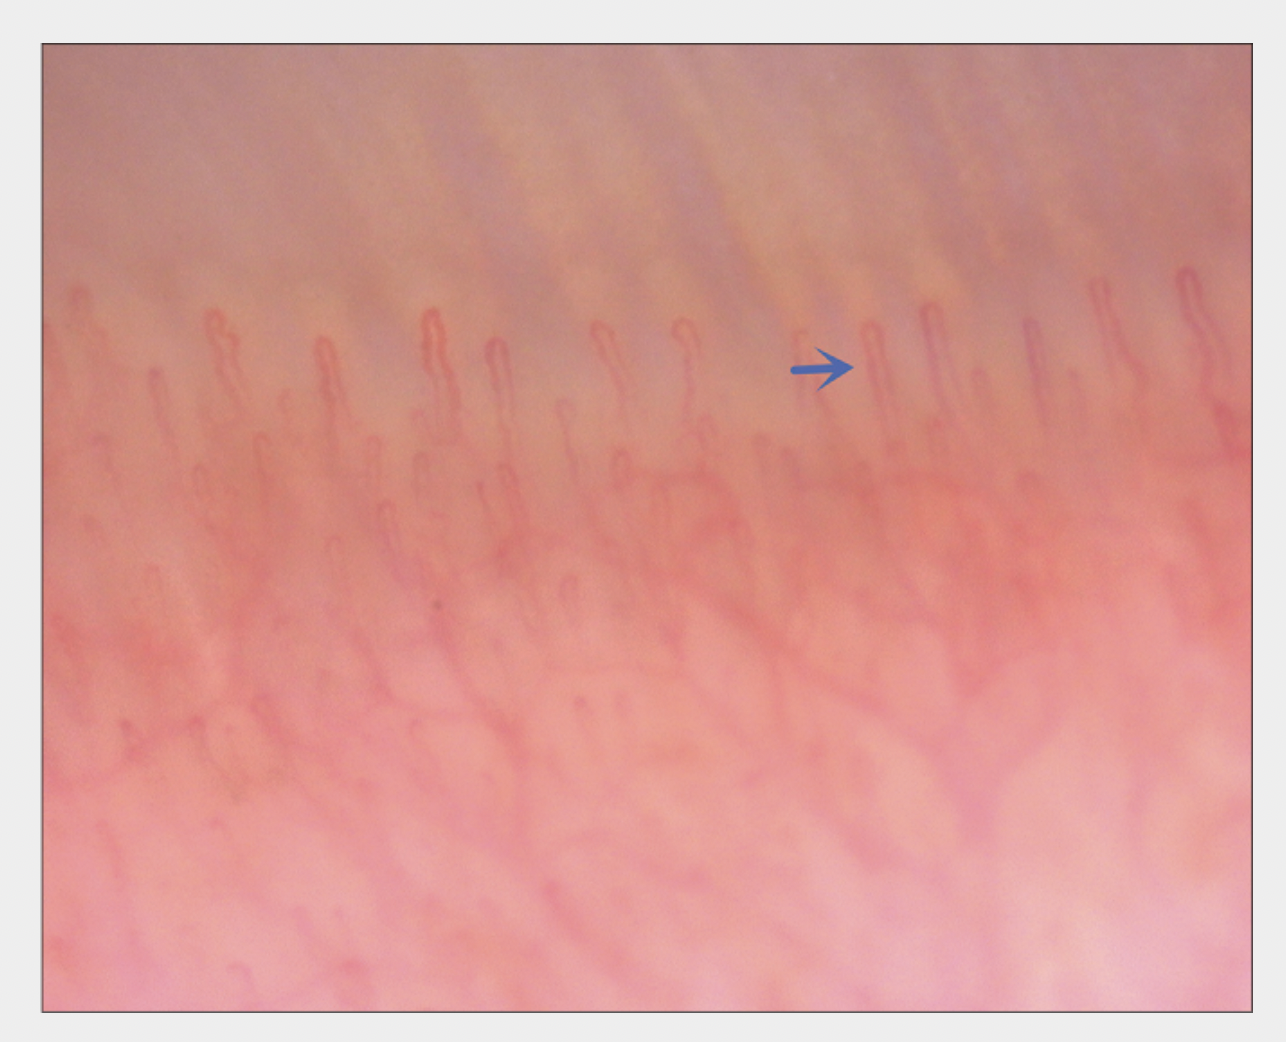

Normal capillaries. this image is a helpful reference. Source: Cao L et al. Nailfold capillaroscopy alterations in androgenetic alopecia: A cross-sectional study. Indian J Dermatol Venereol Leprol. 2022 Feb 28;1-7. Image shown with creative commons license.

BUSHY CAPILLARIES

Bushy capillaries are More Common in Nail Capillaries from Patients with Androgenetic Alopecia Compared to Controls. Source: Cao L et al. Nailfold capillaroscopy alterations in androgenetic alopecia: A cross-sectional study. Indian J Dermatol Venereol Leprol. 2022 Feb 28;1-7. Image shown with creative commons license.

BIZARRE CAPILLARIES

Bizarre capillaries are More Common in Nail Capillaries from Patients with Androgenetic Alopecia Compared to Controls. Source: Cao L et al. Nailfold capillaroscopy alterations in androgenetic alopecia: A cross-sectional study. Indian J Dermatol Venereol Leprol. 2022 Feb 28;1-7. Image shown with creative commons license.

DILATED CAPILLARIES

Dilated capillary areas are More Common in Nail Capillaries from Patients with Androgenetic Alopecia Compared to Controls. Source: Cao L et al. Nailfold capillaroscopy alterations in androgenetic alopecia: A cross-sectional study. Indian J Dermatol Venereol Leprol. 2022 Feb 28;1-7. Image shown with creative commons license.

DISORGANIZED CAPILLARIES

Disorganized capillary areas are More Common in Nail Capillaries from Patients with Androgenetic Alopecia Compared to Controls. Source: Cao L et al. Nailfold capillaroscopy alterations in androgenetic alopecia: A cross-sectional study. Indian J Dermatol Venereol Leprol. 2022 Feb 28;1-7. Image shown with creative commons license.

AVASCULAR CAPILLARY AREAS

Avascular areas are More Common in Nail Capillaries from Patients with Androgenetic Alopecia Compared to Controls. Source: Cao L et al. Nailfold capillaroscopy alterations in androgenetic alopecia: A cross-sectional study. Indian J Dermatol Venereol Leprol. 2022 Feb 28;1-7. Image shown with creative commons license.